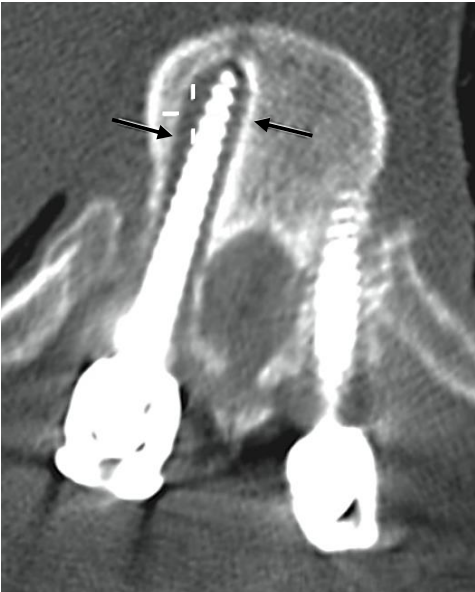

Assinale a alternativa que corresponde a complicação pós operatória na imagem abaixo.